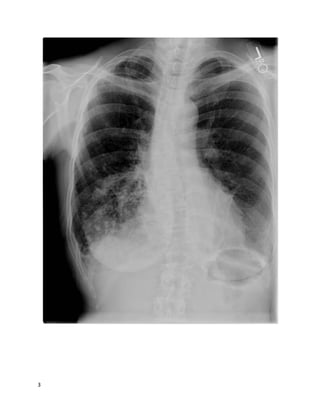

You receive an email from a colleague asking for a "curbsideconsult." You haven't

heard the story or your colleague's question yet, but to frame your thinking, you

quickly glance at the images she's attached to the email.

Based on these images, what's the most likely clinical scenario?

We feelthat A is the best answer.

The chest X-ray shows reticulonodular opacities, a nonspecific abnormal finding.

The axial CT cuts show:

 Small nodules in a lymphangitic pattern, i.e., touching the pleura/fissures

 Pleural effusions with an irregular, nodular contour

9

 Irregular thickening of the interlobular septa

 Peribronchovascular thickening

All these findings are consistent with this patient's diagnosis of lymphangitic

carcinomatosis(LC): diffuse metastatic spread of cancer to the lungs, where it

diffusely infiltrates and obstructs lymphatic channels. 80% of cases are due to

adenocarcinomas, most often from a primary cancer of the breast, lung, or colon.

This case of LC was from a primary pancreatic adenocarcinoma.

Chest films are usually normal in lymphangitic carcinomatosis.